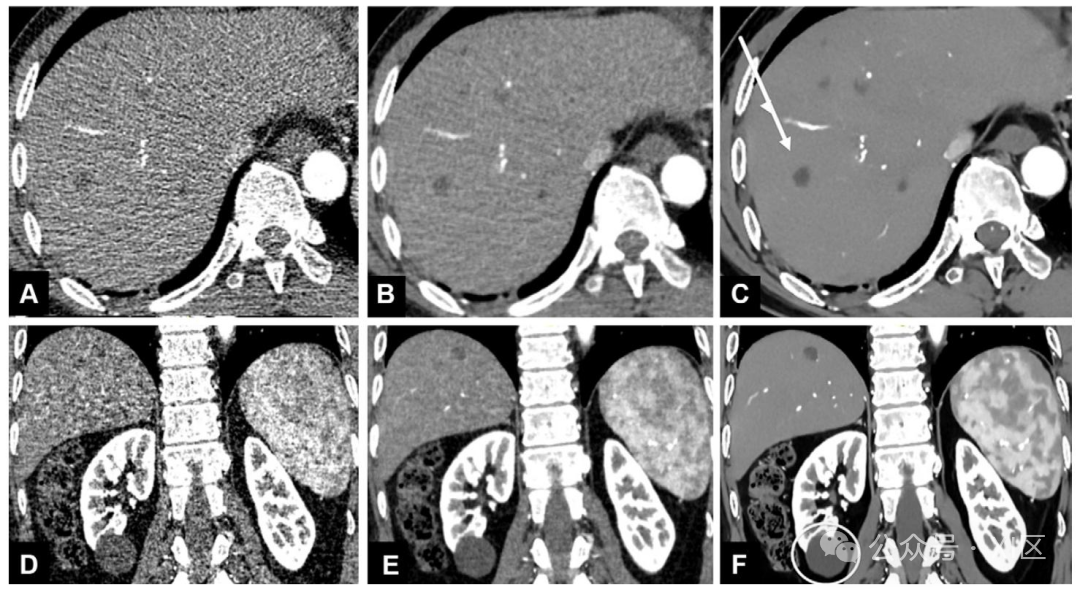

48 岁男性直肠癌肝转移患者的轴位增强双能量 CT(DECT)图像。采用 ADMIRE 技术(西门子医疗)将 DECT 数据重建为线性融合图像(A 图),融合系数为 0.6(80kVp 占 60%,150kVp 占 40%);通过噪声优化虚拟单能量图像重建算法生成 40 千电子伏特(keV)虚拟单色图像(B 图);再采用厂商无关 DLR 方法(ClariCT.AI)重建中等强度 40keV 虚拟单色图像(C 图)。线性融合图像(A 图)的窗宽 / 窗位调整为 300/40,虚拟单色图像(B 图)调整为 600/150。线性融合图像的病变对比增强效果较差(A 图);40keV 虚拟单色图像的对比增强效果更优,但图像噪声较高(B 图);而经 ClariCT.AI DLR 重建的图像,噪声显著降低,病变显影度明显提升(C 图)。

轴位(A-C 图)和冠状位(D-F 图)增强 CT 图像显示,从 FBP(A、D 图)到混合迭代重建技术(B、E 图),再到 DLR AIIR 技术(C、F 图),低衰减肝病变的显影度逐步提升(C 图箭头所示)。AIIR DLR 技术显著改善了单纯肾囊肿的内部纹理(F 图圆圈所示),使其呈现明显的均一性,但可能对图像噪声纹理过度校正,导致肝实质纹理过度平滑。